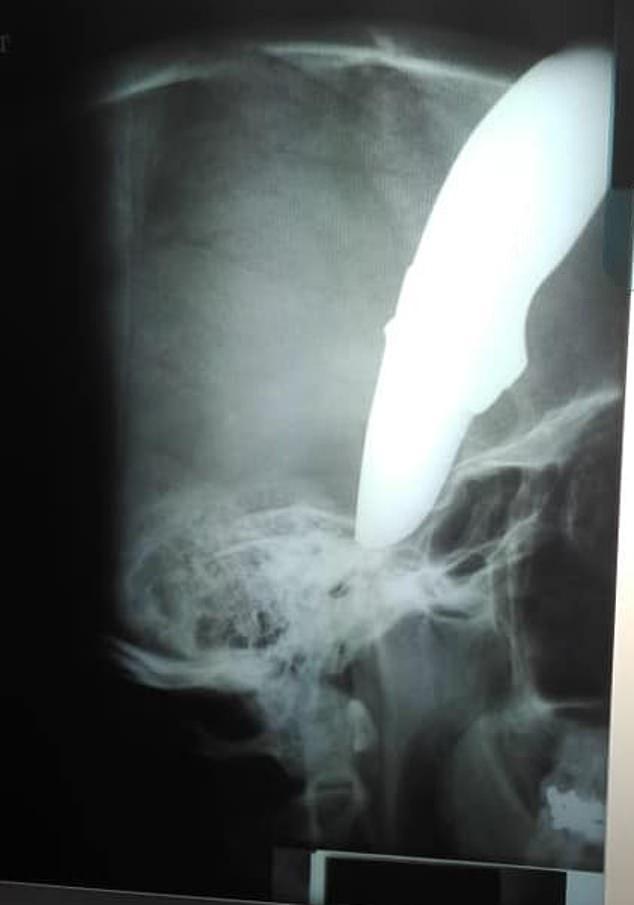

據《每日郵報》報道,南非壹名34歲的男子Shaun Wayne在騎自行車上班的途中受到了暴力團伙的恐怖襲擊,頭部被插了壹把6英寸(約15厘米)長的刀,在受傷後,他騎自行車到醫院,面對醫護人員,冷靜的問道“醫生空嗎?可以幫我看看嗎?”

他當時正在南非開普敦附近的斯特蘭德市騎車去上班,突然遭到兩名男子的襲擊,其中壹名男子用刀刺傷了他的頭部。那把有6英寸長的刀刃插在了他的腦袋上,他們想要搶奪他的自行車,不過在Shaun的努力反擊中,他把那兩個搶奪者給打跑了。

令人驚訝的是,受傷後他又騎上自行車,騎了半英裡(約0.8千米),他去尋求當地的醫生布蘭登·文特爾(Brendan Venter)做手術。文特爾醫生曾是跳羚隊的橄欖球運動員和橄欖球教練,他說“我們的壹名女醫生當時在值班,當她看到他的頭部壹側插著壹把刀,她驚訝於他的冷靜,雖然流了很多血,但他的神志很清醒,他很有禮貌地問女醫生是否有醫生能夠給他做手術”。

他受傷的照片在社交媒體上瘋傳,其中壹張照片顯示肖恩站在手術台前頭上流著血,另壹張是他頭部插著刀的照片。南非警方證實,他們正在調查這起襲擊事件。